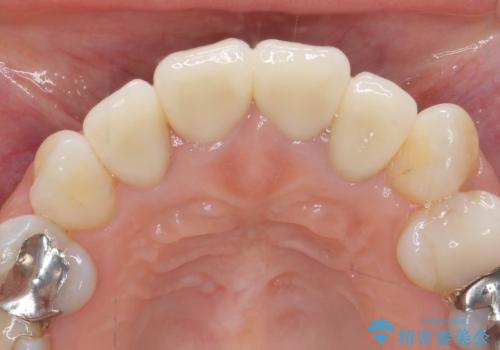

- 52.8万円(ジルコニアクラウン×4・仮歯×4)費用は治療当時の料金となります

自然で美しい前歯の仕上がりとなり、大変満足していただくことができました。